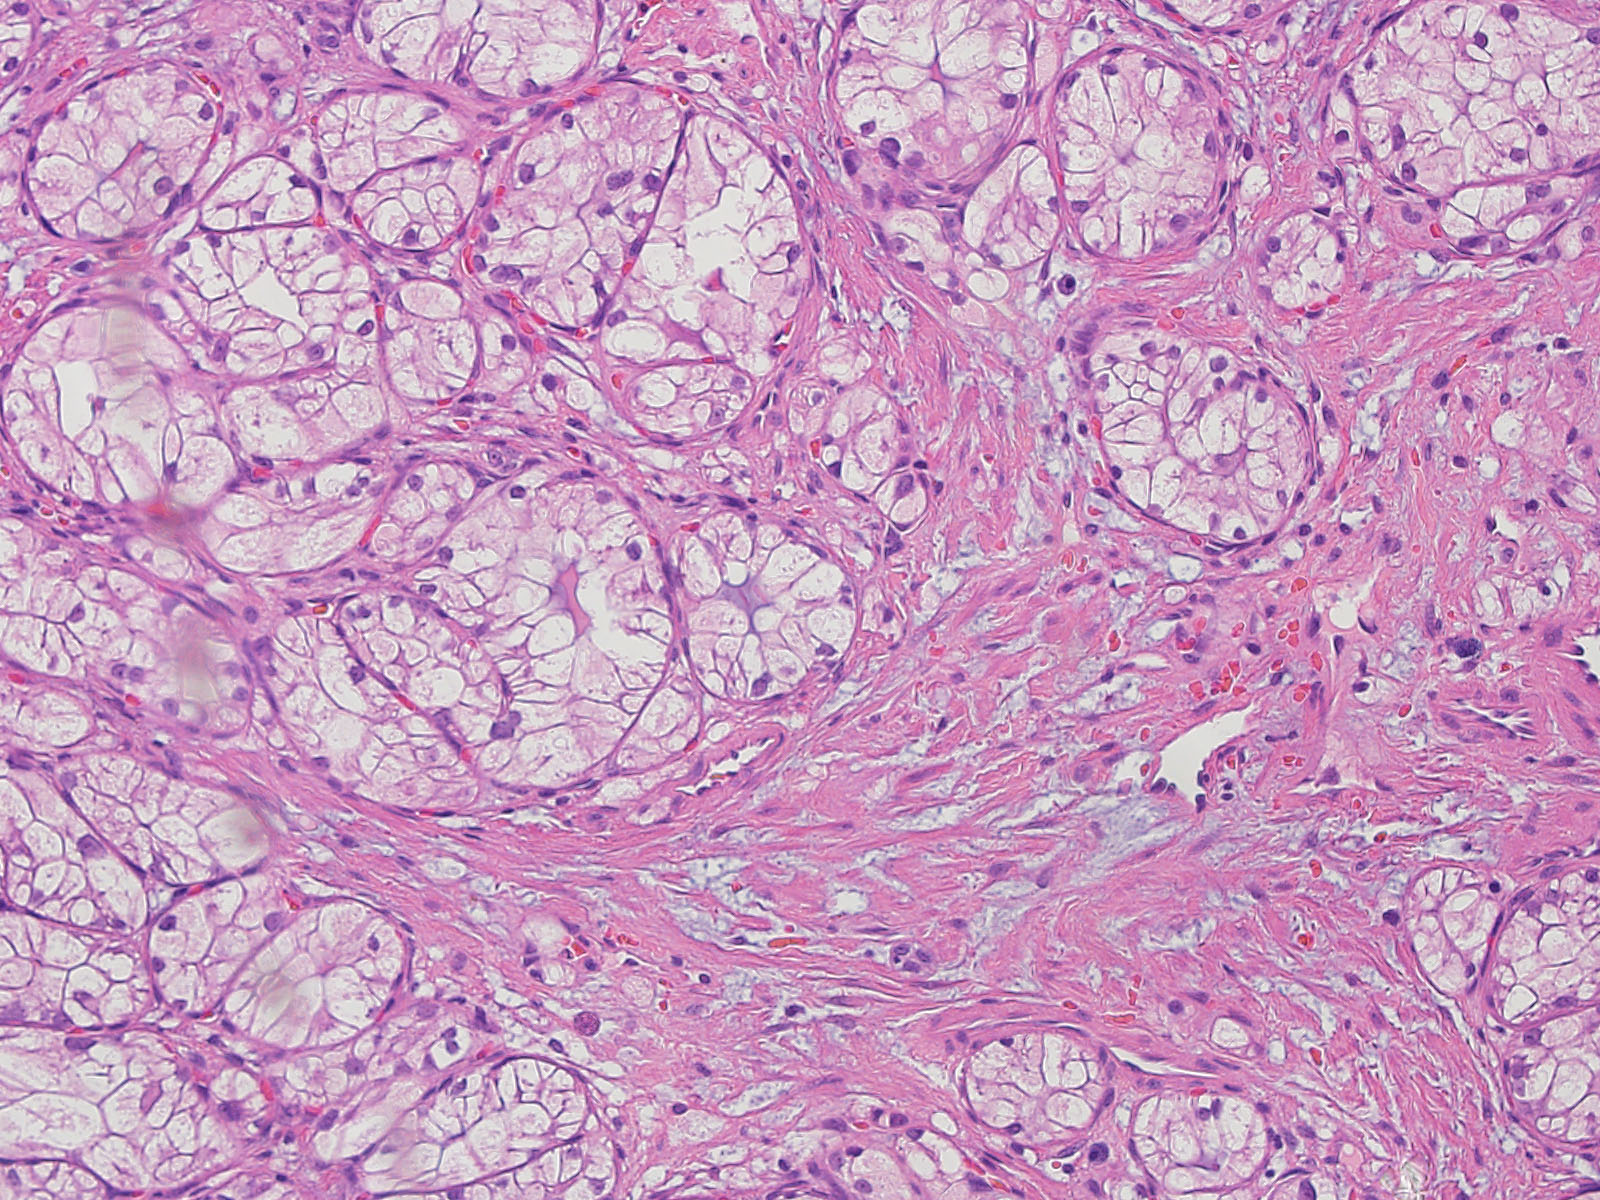

Classification of renal tumors

Case ID: 778